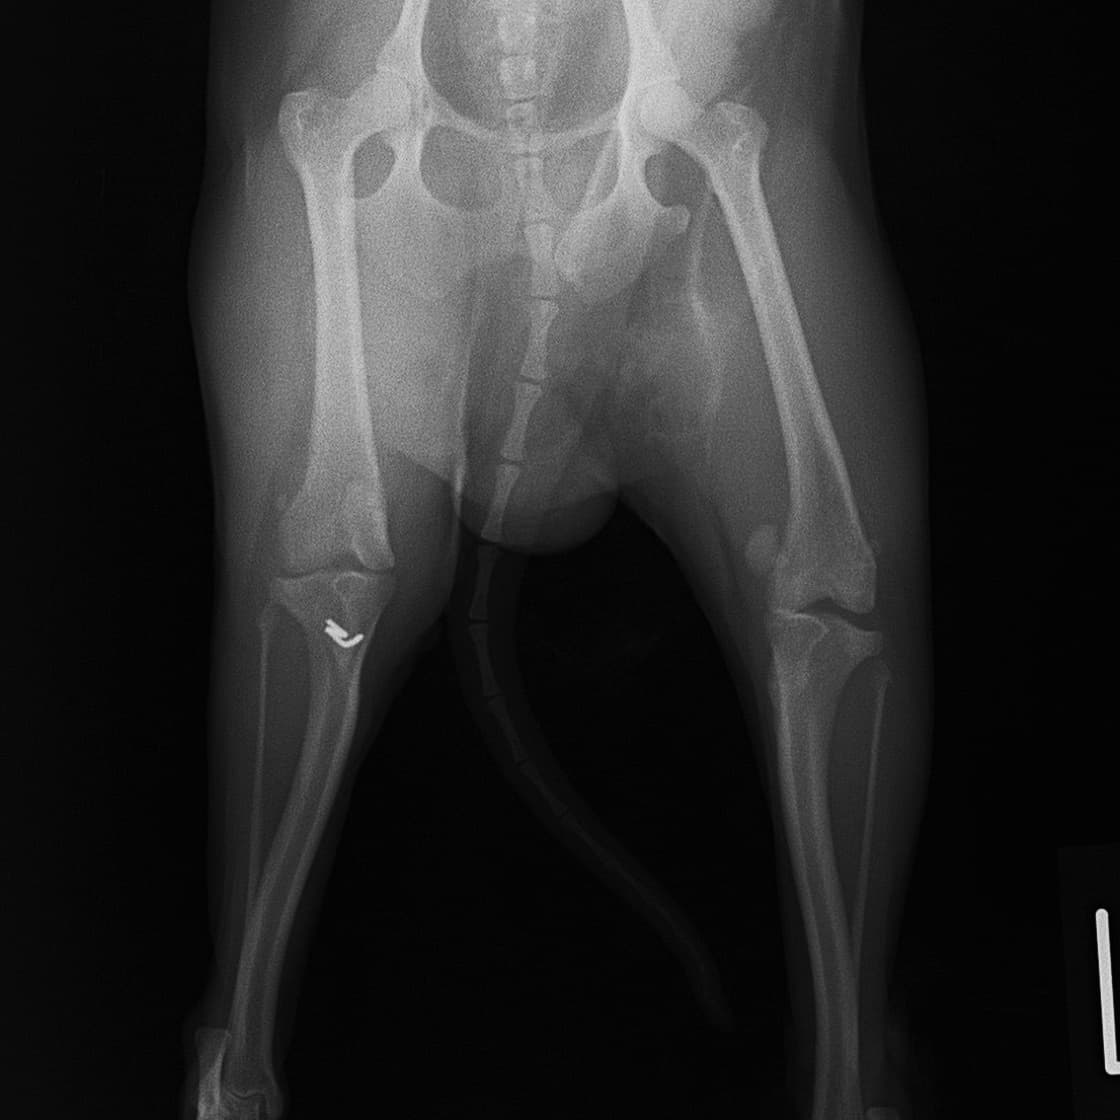

■ 症例22 ポメラニアン 1歳5か月 去勢雄

左後肢の挙上を主訴に来院した。整形学的検査、レントゲン検査より左右の膝蓋骨脱臼(左GradeⅡ〜Ⅲ、右Grade Ⅱ)を認めた。また、脛骨の前方引き出し試験の際に、引き出し兆候は認められないものの、疼痛が認められたため、前十字靭帯の損傷が疑われた。術中における、目視および関節内の操作によって、前十字靭帯の損傷や過伸展といった異常が認められなかったため、膝蓋骨脱臼の整復のみ実施した。手術手技は縫工筋及び内側広筋の解放、脛骨粗面の外側転位、滑車ブロック形造溝術、内外側関節包の縫縮を実施した。本症例は跛行もなく経過良好である。しかし、頸骨高平部の角度(TPA)が 右26.2°、左24.9°であり、解剖学的に前十字靭帯損傷のリスクが高いことから今後の経過に注意が必要である。